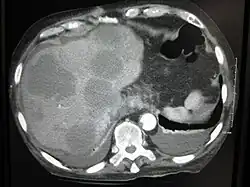

Eine Lebermetastase oder Leberfilia ist eine bösartige Tumorabsiedlung (Metastase, Tochtergeschwulst) in der Leber.

Meist finden sich bei genauem Suchen mehrere Metastasen. Einzelmetastasen sind eher selten. Sie lassen sich mittels Ultraschall, CT und MRT darstellen.